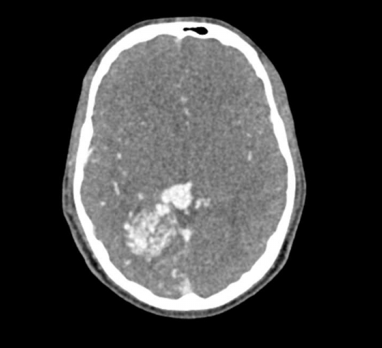

El maniquí de cabeza proporciona una simulación extremadamente realista de una angiografía por TC de cabeza y cuello (con contraste arterial) de un paciente con una malformación arteriovenosa en el lado derecho. El maniquí se entrega fiel a la escala original e incluye la columna cervical hasta la placa base de la quinta vértebra cervical.